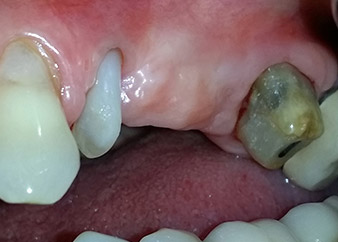

One month later, on the day of surgery, pain and inflammation at tooth 24 were minimal, but mobility of Miller class 2 was still present. After opening the flaps and cleaning the periapical and peri radicular infected tissue, the extent of the bone defect became obvious (Figs. 2 and 3).

At the buccal root, all vestibular and distal bone was missing. Attachment was essentially restricted to the palatal root, underlining the preliminary poor prognosis. Tooth 27 also showed a reduced horizontal attachment and a minimal apical rarefaction (cf. Fig. 1) without clinical symptoms.

total loss of bone and attachment

Fig. 2 and 3: After raising flaps, one month after endodontic revision and initiation of full-mouth periodontal therapy, the buccal root of tooth 24 showed a total loss of bone and attachment.